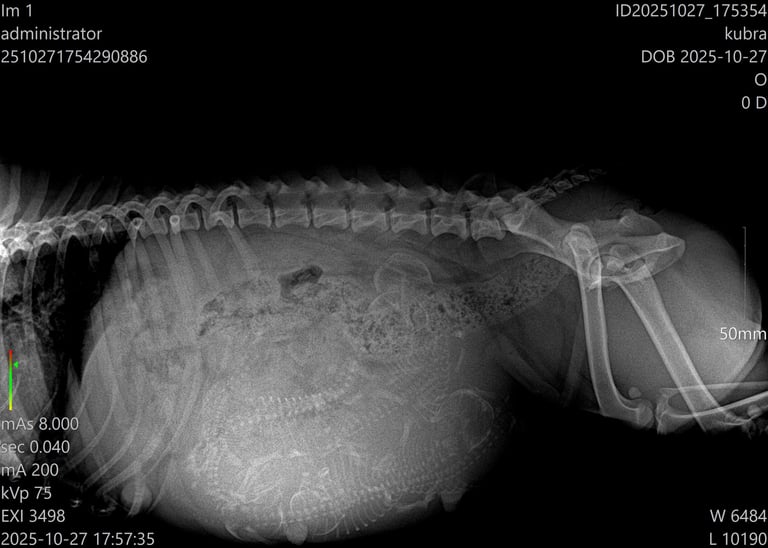

Tra il 55° e il 57° giorno di gravidanza, accompagniamo nuovamente la futura mamma in clinica per effettuare un’ecografia di controllo e una radiografia addominale.

L’ecografia ci permette di monitorare il benessere dei cuccioli, osservando il battito cardiaco e le condizioni generali all’interno dell’utero.

La radiografia, invece, ci fornisce un’informazione fondamentale: il numero esatto dei cuccioli in arrivo. Questo dato è molto utile per prepararsi al parto e seguire con attenzione ogni fase della nascita.